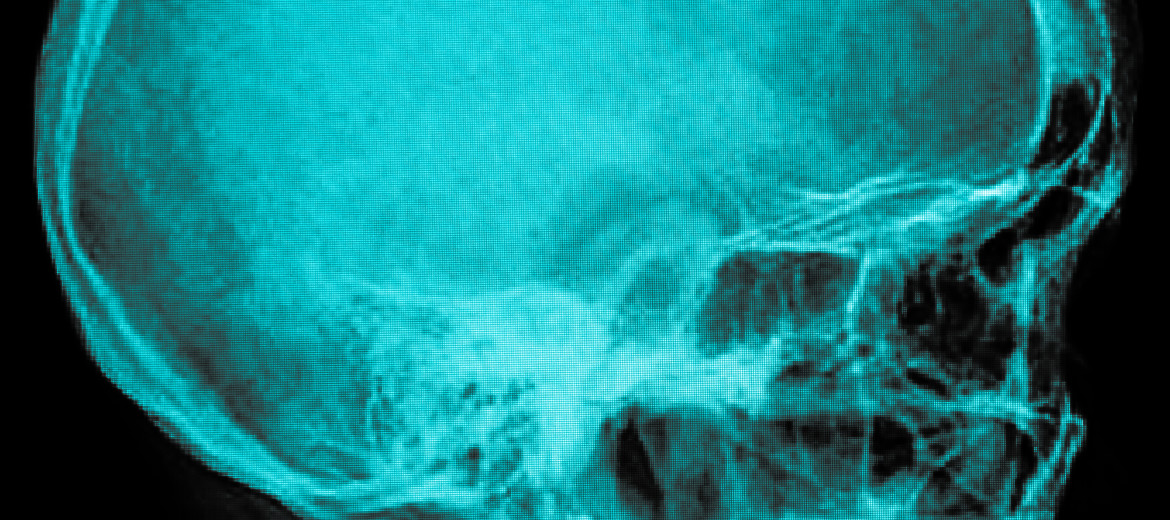

Hackettstown – The practice has established The Concussion Center at The Orthopedic Institute of New Jersey. The goal at The Center is to educate, provide baseline testing, diagnose and treat patients who may have suffered a concussion. In recent years, a strong focus has been placed on the prevention and treatment of concussions. Many parents and athletes have been appropriately concerned about participating in sports, particularly those sports that have a higher potential for head injuries.  Among professional sports, a week rarely passes without an incident, lawsuit, or significant concern related to concussions and concussive care and testing. As more people become aware of the topic, better preventative care, treatment and proper plans for returning to action are being put in place and athletes should be taking advantage of this.   We believe that through the Concussion Center at our Practice, we can assist our patients to become better educated about this condition and provide them with state-of-the- art care. The medical evaluation of a concussion can be extremely complex because concussive injuries can affect many different parts of the brain. The development of computerized neuropsychological or baseline testing has become a very useful tool to evaluate an athlete’s memory, concentration and reaction times. Computerized neuropsychological testing does not replace or eliminate the need for a specialized doctor evaluation but it helps to standardize and simplify the return to play process. Athletes at any level who are tested before a season begins can establish a baseline related to his or her cognitive functioning.  If during the course of athletic participation an athlete suffers a possible concussion, they can then be retested to determine if there are any deficits.  Appropriate care can then follow.   Neuropsychological/BaselineTesting is conducted at The Orthopedic Institute of New Jersey by appointment. No athlete, coach or parent should ever consider a concussion to be an insignificant event. The majority of serious brain injuries related to a concussion occur when an athlete suffers repeat head trauma while still symptomatic from an undiagnosed concussion. Only a trained medical professional can evaluate a concussion and in New Jersey, only a physician with specialized concussion training can diagnose or rule out a concussion.